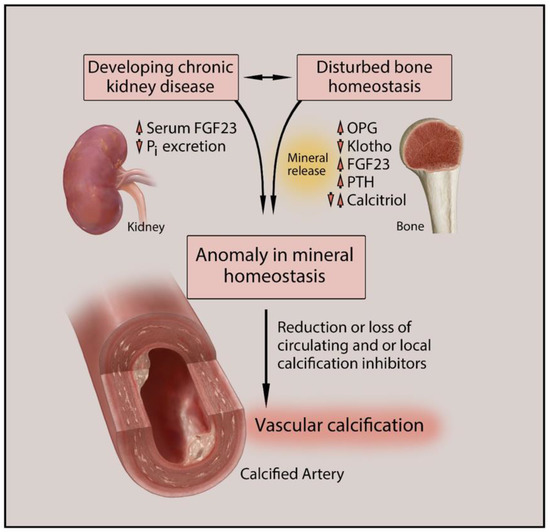

The calcium is stored in our bones. Drinking plenty of water could help you to lower your calcium blood levels and avoid kidney stone formation. Eliminate foods that contain methylxanthines, such as coffee, black.

Kidney calcification calcium deposits can also. When blood levels of calcium fall too low, the bones release calcium into the. It involves removing a portion of the pericardium.